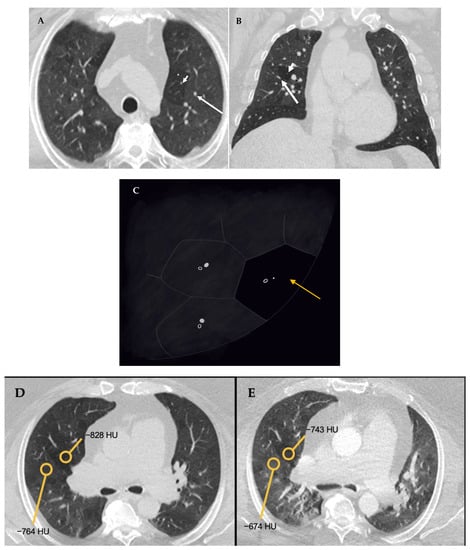

- Baqir, M.; White, D.; Ryu, J.H. Emphysematous changes in hypersensitivity pneumonitis: A retrospective analysis of 12 patients. Respir. Med. Case Rep. 2018, 24, 25–29. [Google Scholar] [CrossRef]

- Miller, W.T.; Chatzkel, J.; Hewitt, M.G. Expiratory air trapping on thoracic computed tomography. A diagnostic subclassification. Ann. Am. Thorac. Soc. 2014, 11, 874–881. [Google Scholar] [CrossRef]

- Hochhegger, B.; Sanches, F.D.; Altmayer, S.P.L.; Pacini, G.S.; Zanon, M.; Guedes, A.C.B.; Watte, G.; Meirelles, G.; Barros, M.C.; Marchiori, E. Air trapping in usual interstitial pneumonia pattern at CT: Prevalence and prognosis. Sci. Rep. 2018, 8, 17267. [Google Scholar] [CrossRef]